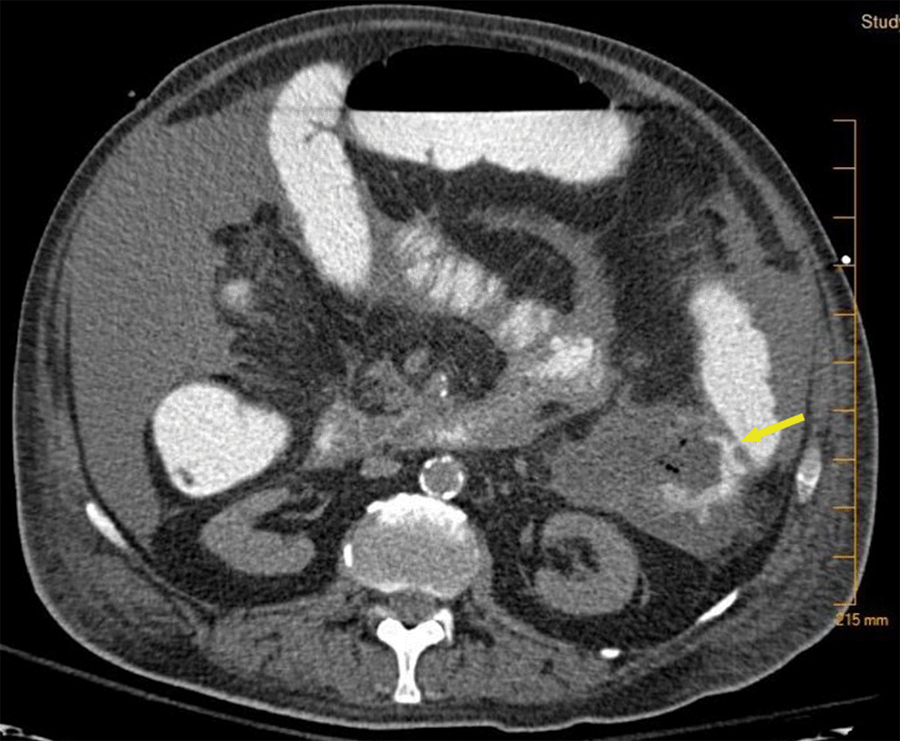

Repeat CT abdomen and pelvis with oral was performed to localized fistula and guide surgical planning. This showed contrast extravasation into pancreatic collection (Figure 2) with a fistulous connection to the splenic flexure of the colon (Figure 3). MRCP was considered for evaluation, but the patient was too unstable for the MRI and would not change our treatment plan at this time.

Figure 3. CT Abdomen Pelvis With Oral Contrast Showing Fistulous Connection to Splenic Flexure of the Colon (Yellow Arrow). Published With Permission